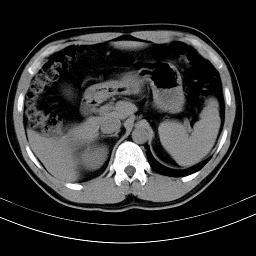

标题: CT18388:肝脏膈肌间隙内大量脂肪密度影 [打印本页]

标题: CT18388:肝脏膈肌间隙内大量脂肪密度影

是脂肪不是气体,有时候会碰到这样的病人,脂肪过多吧。

腹腔脂肪沉积过多

膈下脂肪沉积。

考虑膈下脂肪沉积。

激素治疗的病人容易脂肪沉积